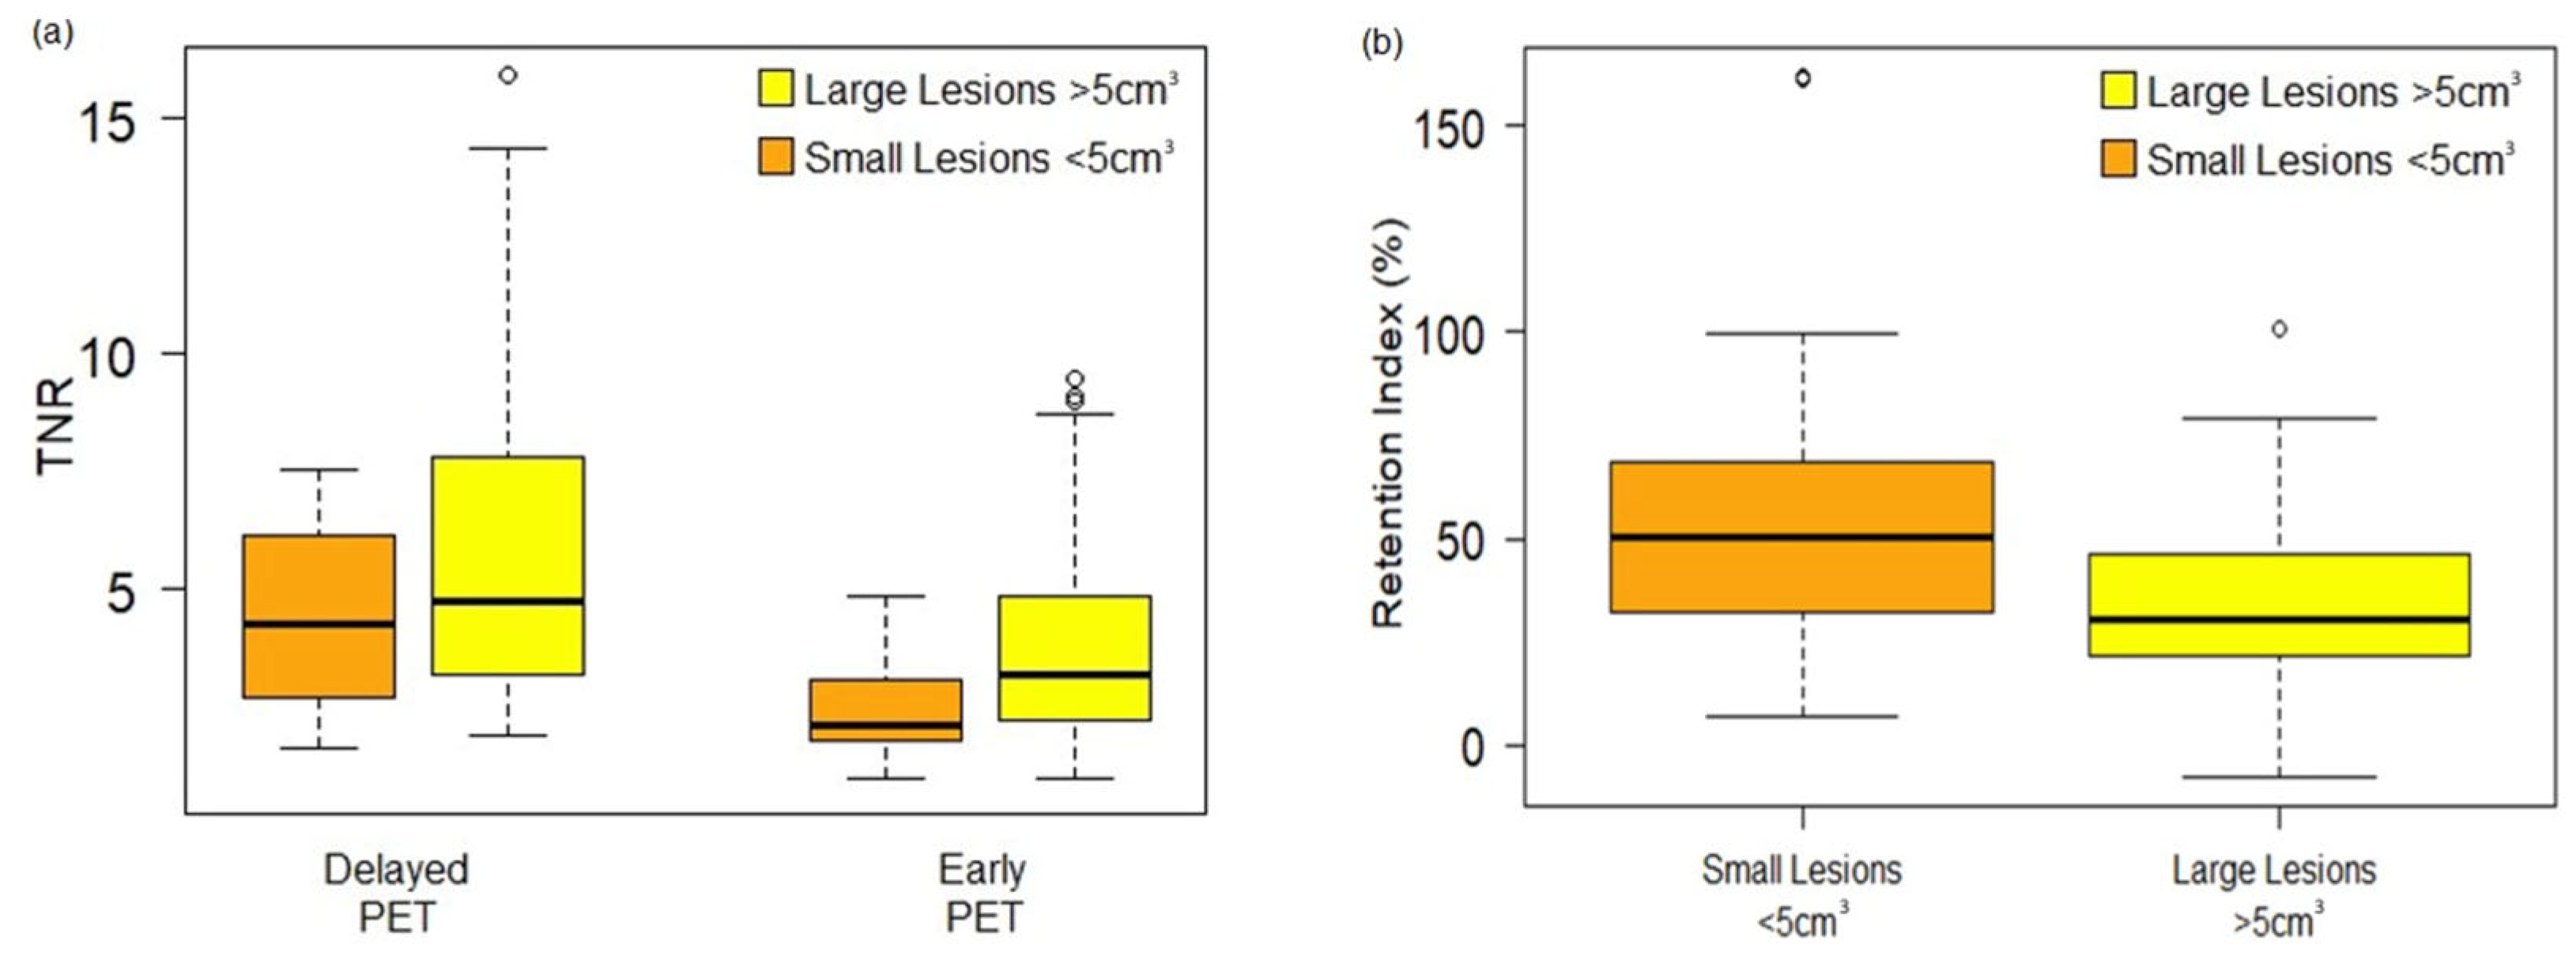

3.3. Semi-Quantitative and Per-Lesion Analysis

4. Discussion